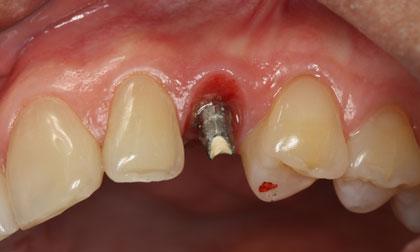

ส่วนความสวยงามโดยเฉพาะบริเวณฟันหน้าที่เกิดอุบัติเหตุ หรือต้องถูกถอนไปจากสาเหตุต่างๆ ทันตแพทย์สามารถใส่รากฟันเทียมทดแทนได้ทันที พร้อมทั้งทำฟันครอบชั่วคราวไว้ประมาณ 6 – 8 อาทิตย์ ก็จะทำการใส่ฟันถาวรได้

ภาพฟิล์ม X-Ray